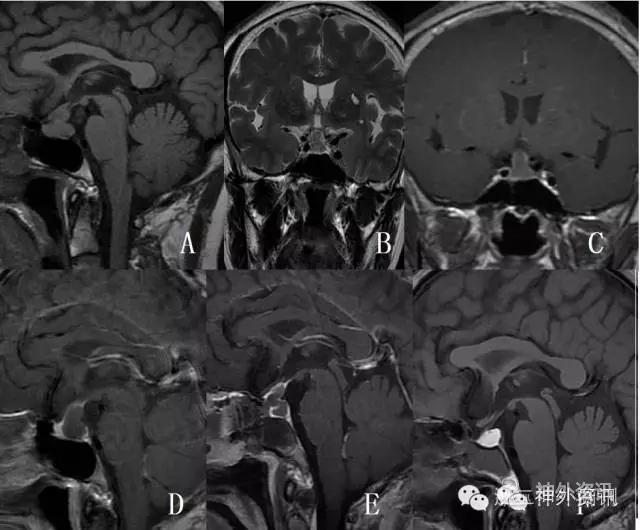

垂体转移瘤比较少见,文献报道约占垂体肿瘤的1%[1]。统计我科2012年3月至2016年5月的资料,共245例转移瘤,只有1例(0.41%)经病理证实为垂体转移癌。患者为女性,65岁,以“头痛1月”入院,垂体MRI发现垂体占位病变(图8A-D),行经蝶显微肿瘤切除术。术前肿瘤标记物正常,术中冰冻及术后常规病理均提示为转移性腺癌,考虑乳腺癌或肺癌转移可能,但PET-CT及乳腺、胸部的相关检查均阴性。术后MRI显示肿瘤全切(图8E),鉴于为转移性肿瘤,术后予局部放疗,44个月随访时一般情况良好,复查垂体MRI示局部囊变,未见复发(图8F)。

图8. 术前MRIT1平扫,T2及T1强化片(A-D),显示垂体肿瘤,强化不明显;术后复查显示肿瘤全切(E);术后44个月(放疗后)复查未见复发(F)。